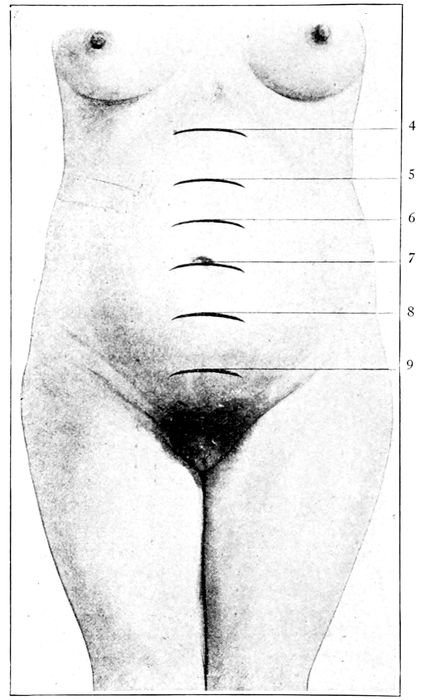

Fig. 28.—Height of the uterus at various months of pregnancy. (Bumm.)